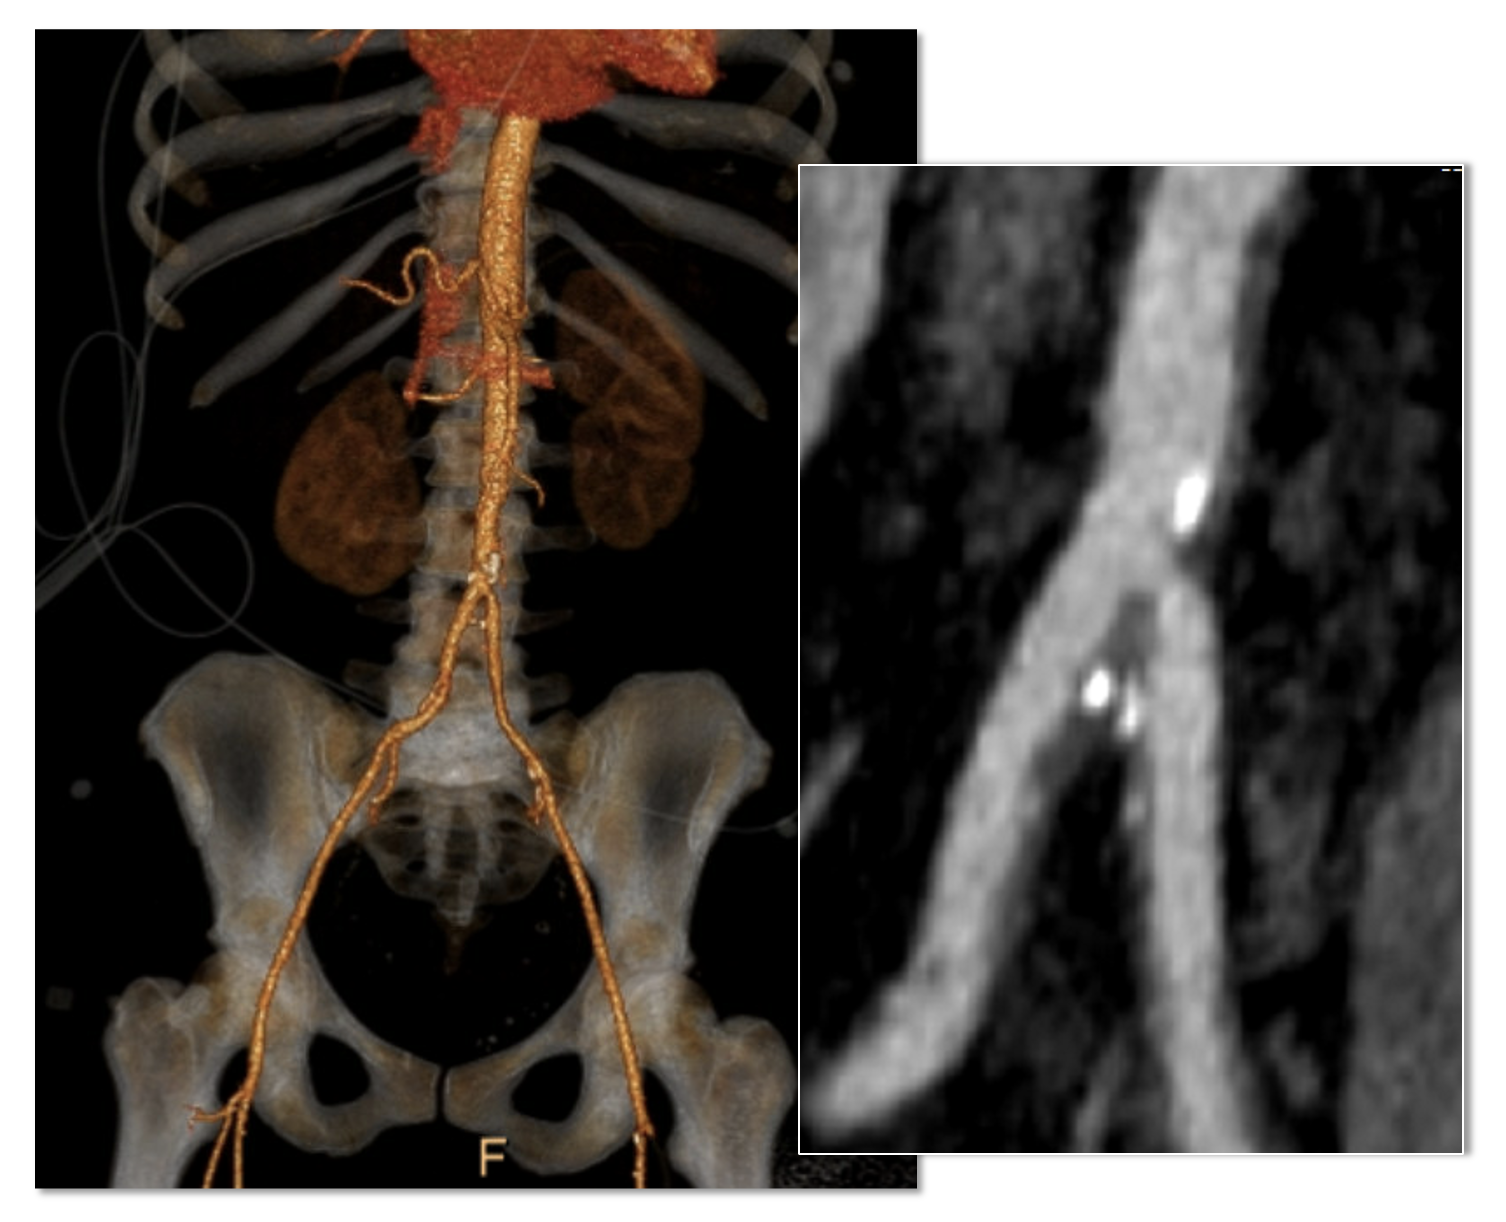

Her baseline CTA in workup of her claudication the year prior to getting stented shows the aorta and iliacs, while open, are small, with aortic lumen diameter reaching 10mm and common iliac lumen diameter at 6mm with diffuse atherosclerosis (below).

The CTA on presentation shows bilateral stent occlusion. A closer look shows the second set of stents extending the original stents both proximally into the aorta (raising the bifurcation) and distally into the external iliac and across the internal iliac origins (white arrows). The internal iliac arteries, despite the stents and on the right thrombus in the stent, supply flow to the external iliac arteries which have not thrombosed.